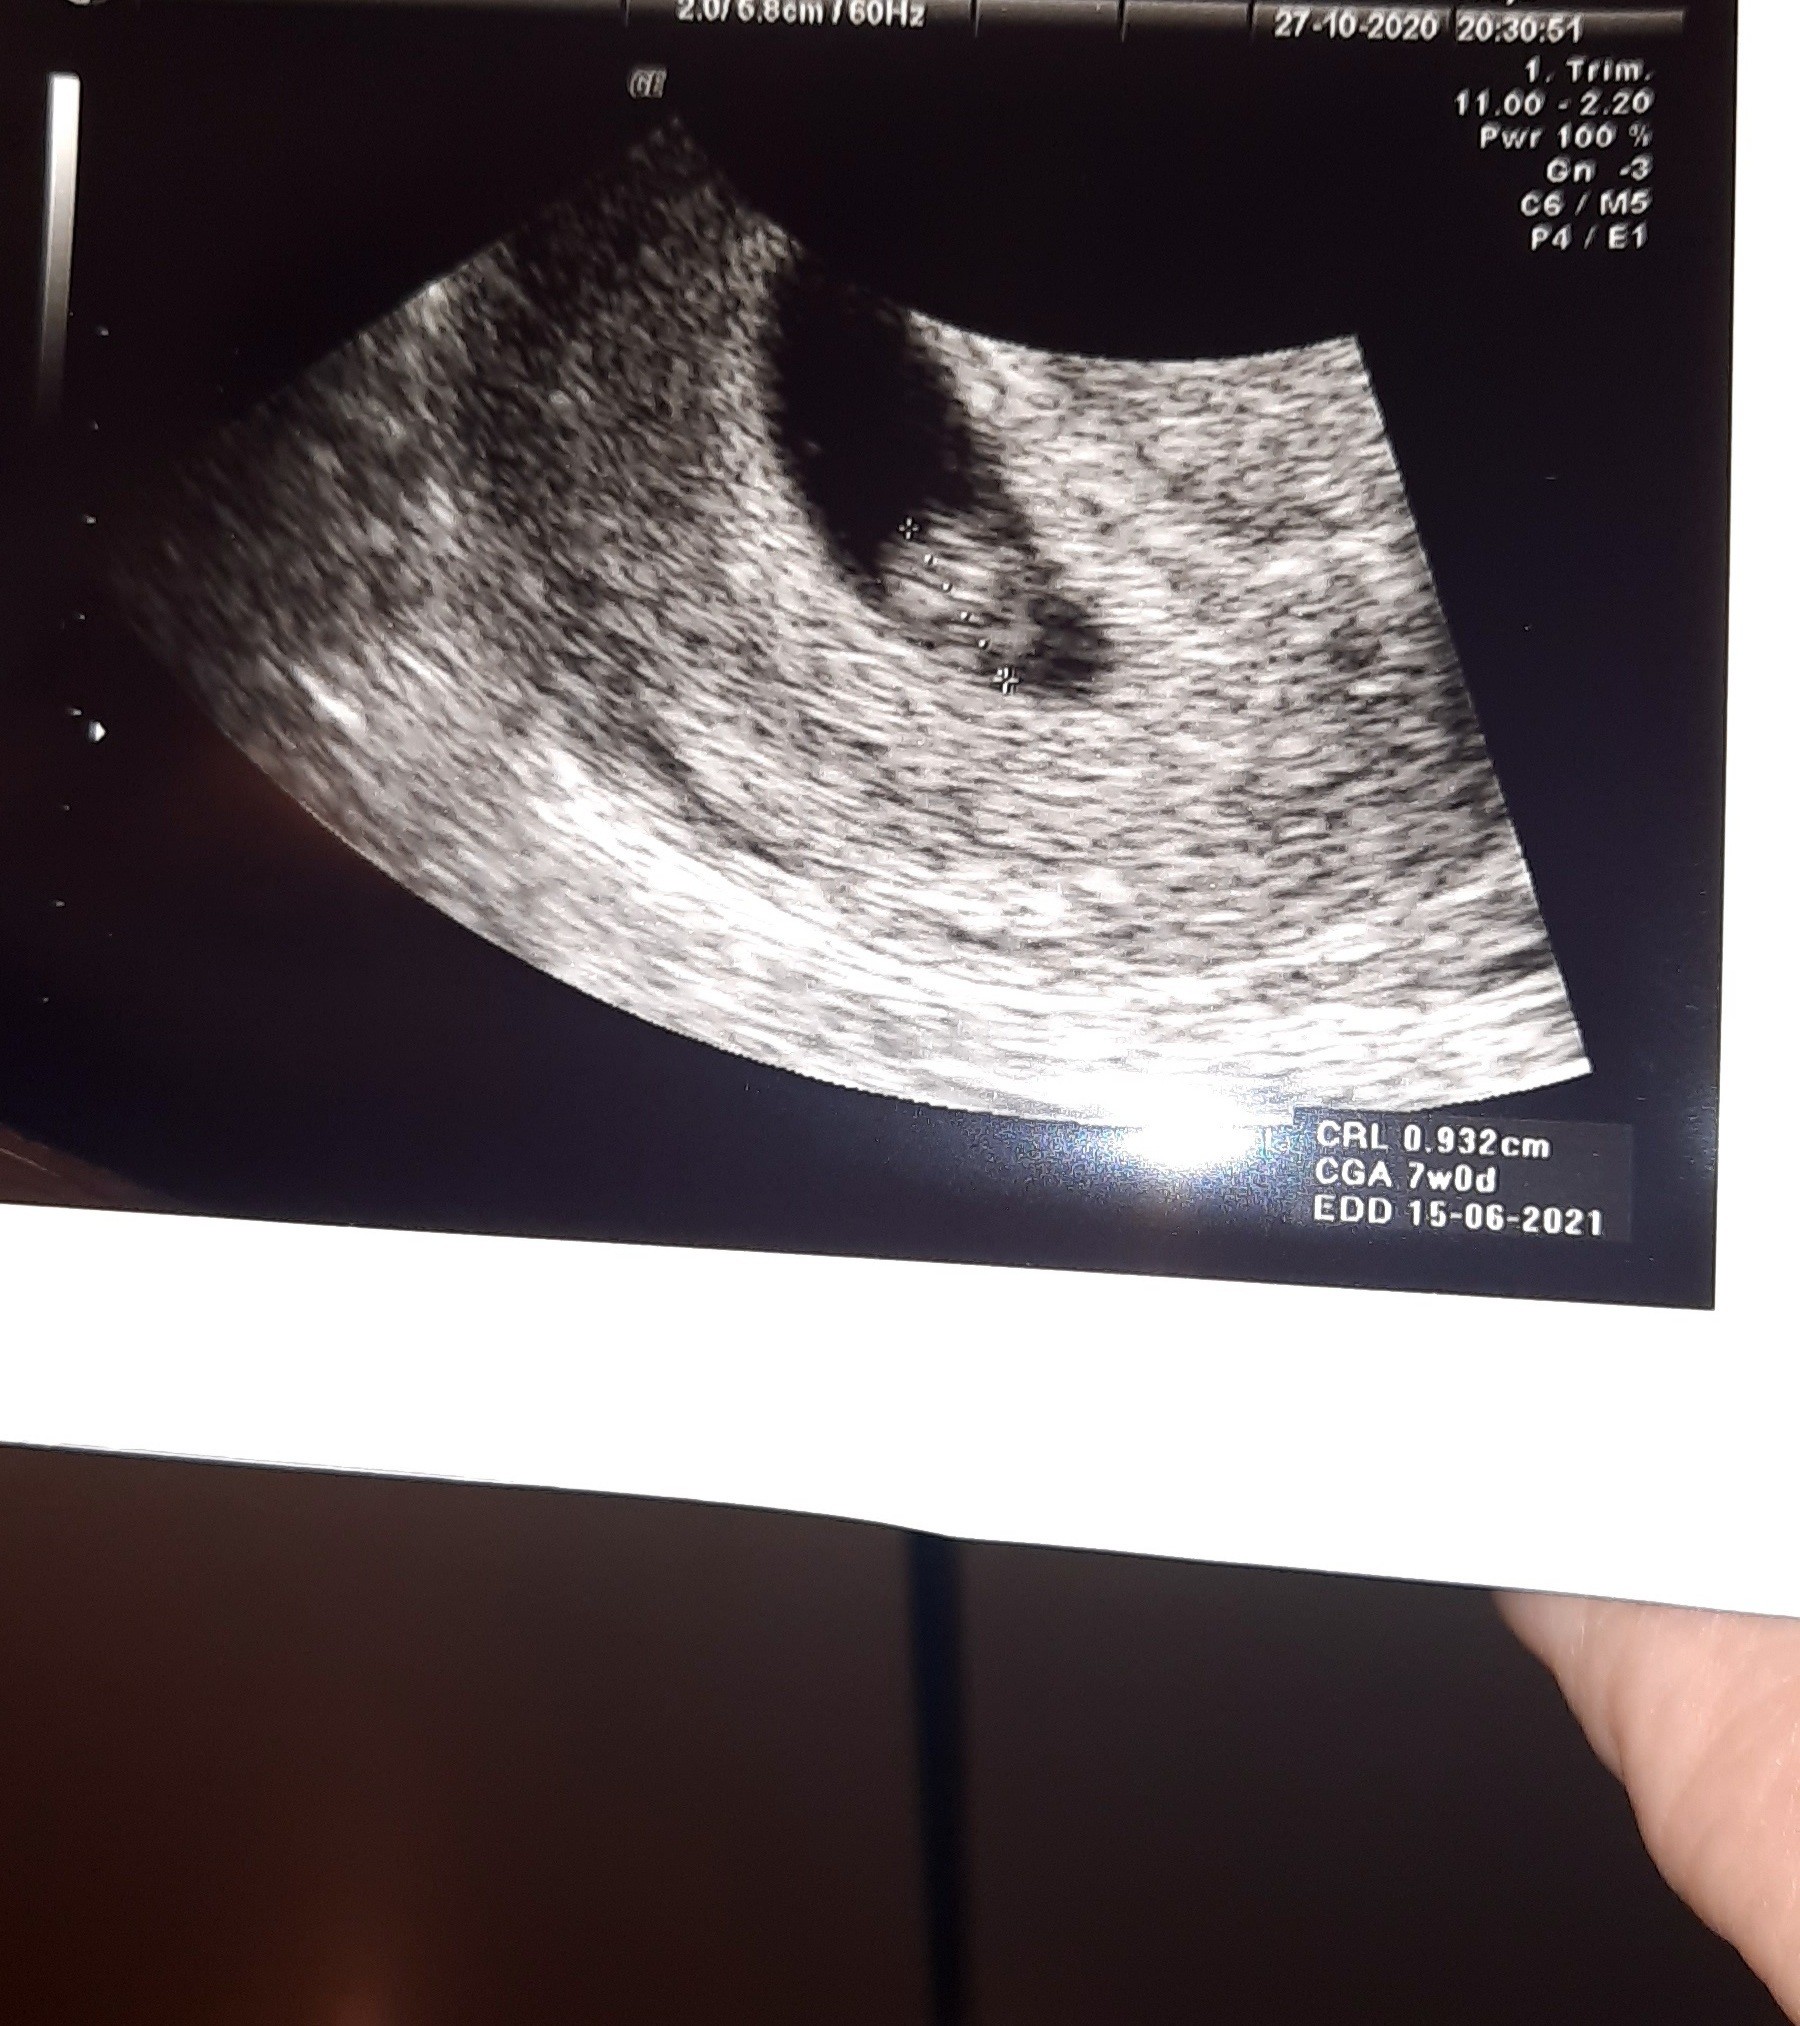

A i zdjecie mojego kropka aczkolwiek w innym ulozeniu byl kropek wiekszy a tu jakis taki malutki:D ale mam tylko jedno zdjecie

Załączniki

• 20201027_211738.jpg

20201027_211738.jpg

625,6 KB · Wyświetleń: 93